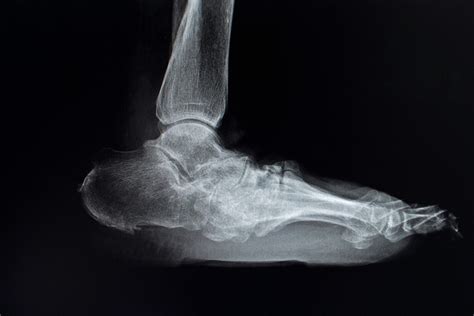

Imaging studies are essential for confirming the diagnosis and assessing the extent of the condition. Common imaging studies include:

• X-rays: To visualize bone structure and detect any fractures or deformities